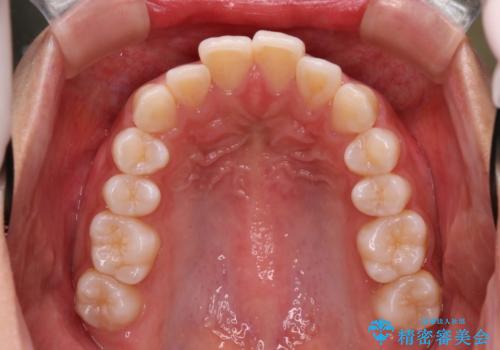

Invisalign インビザラインによる軽度なガタつきの改善